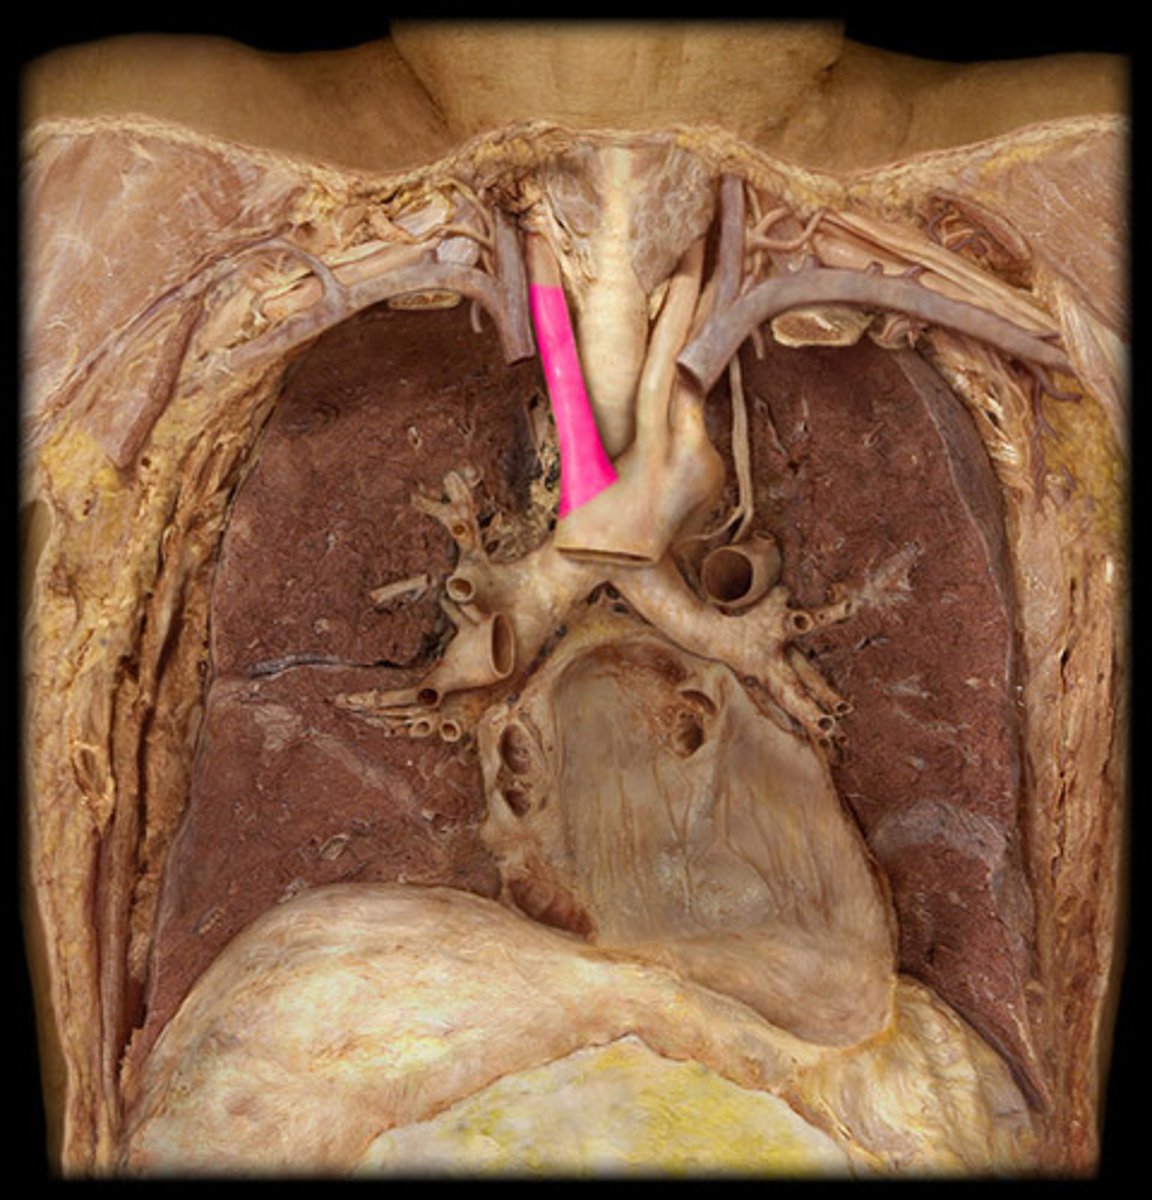

pulmonary trunk

leaves the right ventricle (collective structure)

left pulmonary artery

Identify the vessel

ligamentum arteriosum

vestige of the fetal ductus arteriosus, which shunted blood in the pulmonary trunk away from the lungs in the fetus

superior vena cava

the vena cava drain into the right atrium

posterior side, upper part